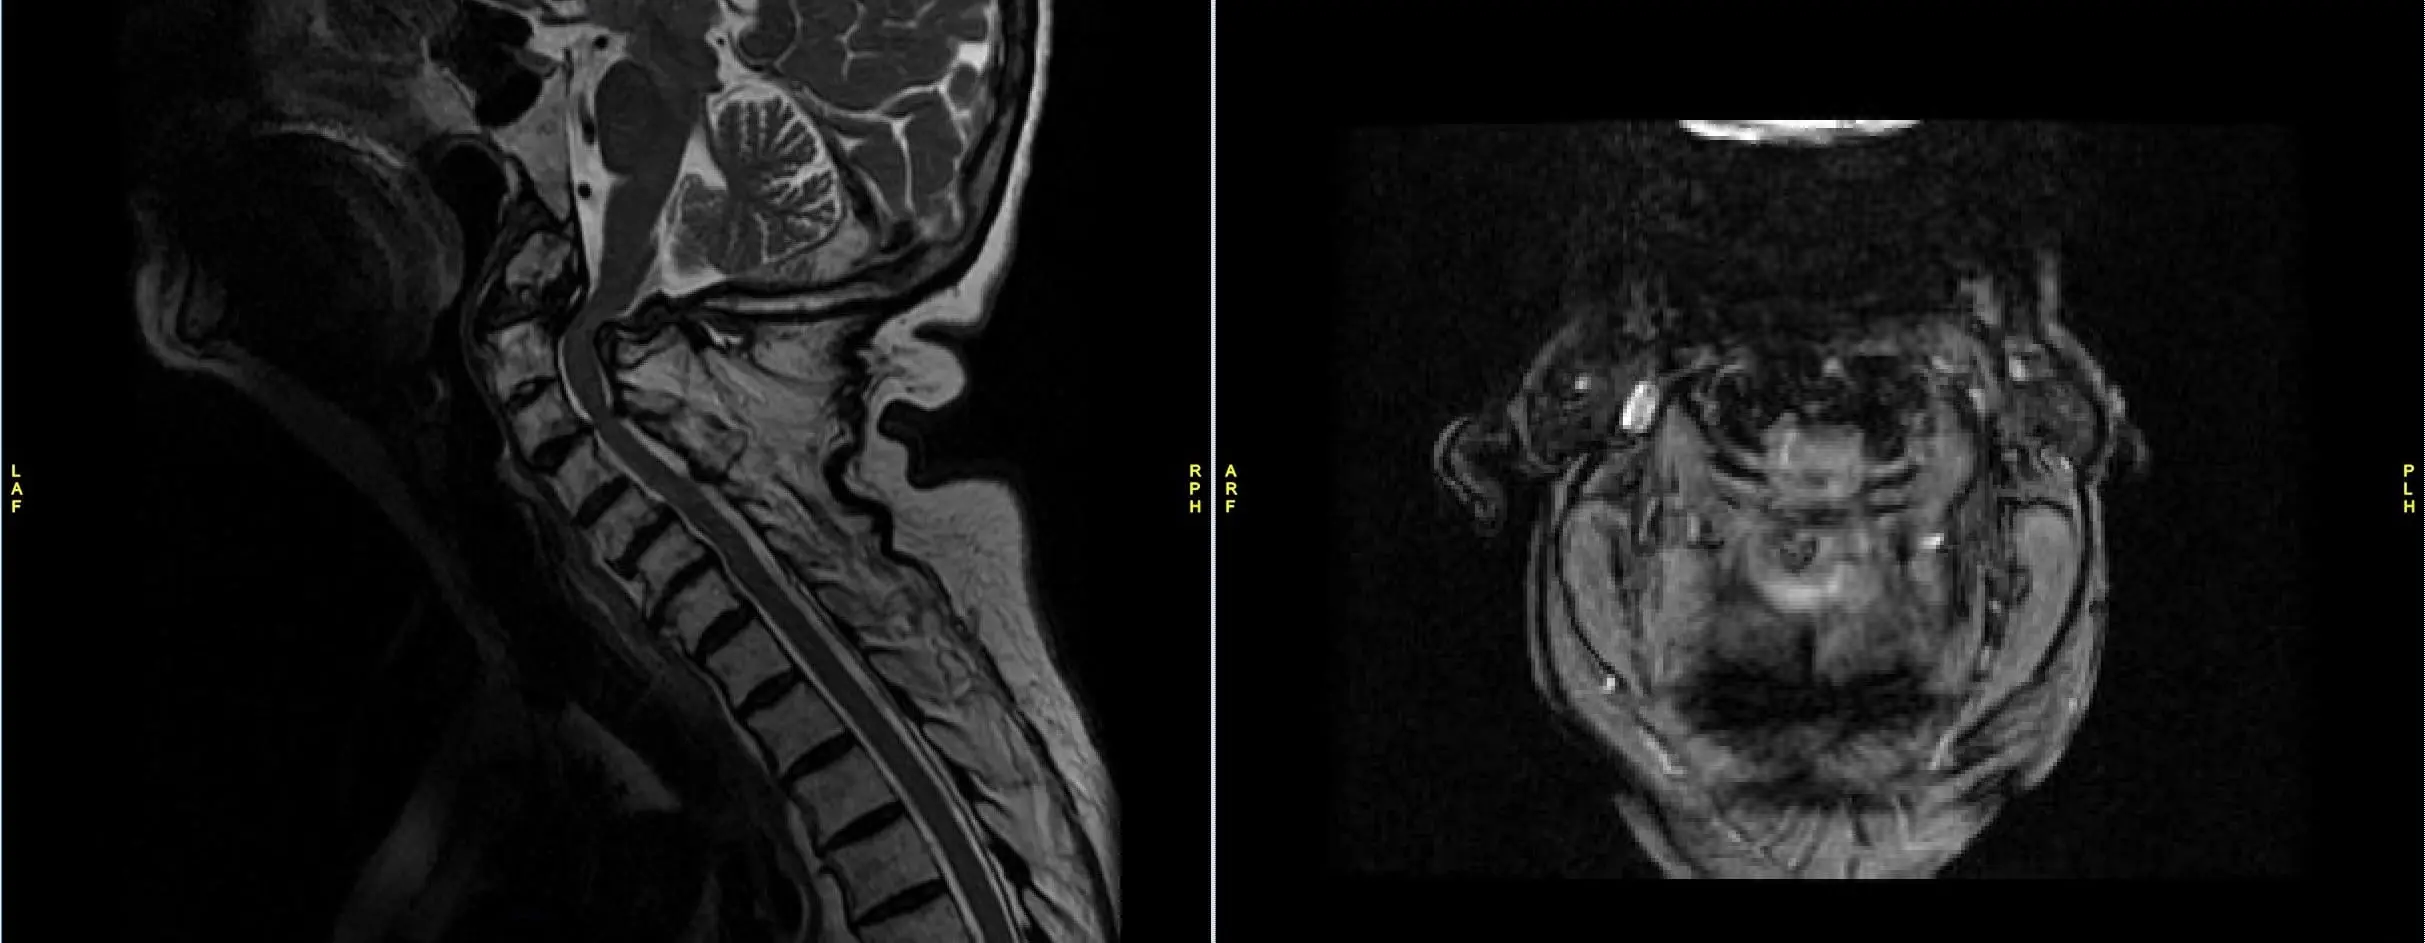

He was having balance issues along with weakness in all 4 extremities. X rays, CT scan and MRI showed a non-union of odontoid fracture with pannus formation and fibrous union, instability with compression of spinal cord at C1-2 level.

After thorough discussion with the patient, an operative management was planned. Posterior C-12 decompression with stabilization with a C1-2 screw and rod fixation was performed.